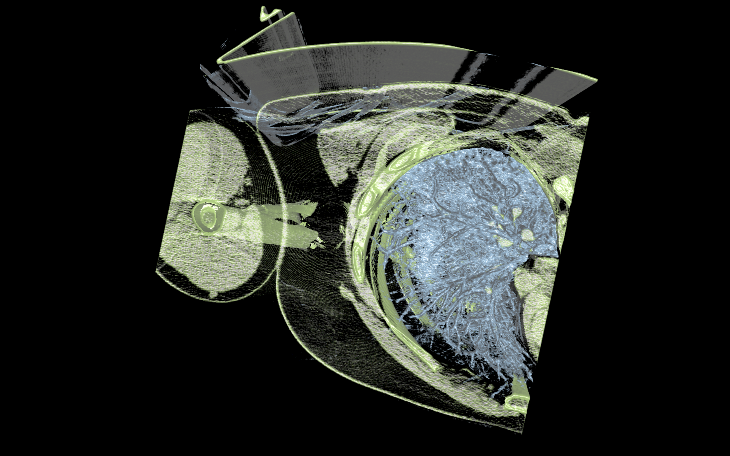

- SPECviewperf